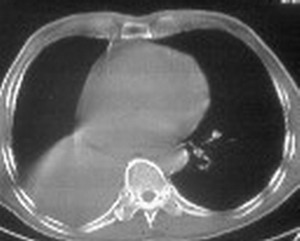

右肺下叶支气管阻塞,右下叶不张,考虑中心型肺癌伴下叶不张

先考虑:右下肺中心型肺癌伴下叶肺不张、胸腔积液

右肺下叶支气管闭塞,中间段支气管狭窄,下叶不张,胸腔及叶间积液.中心型肺癌伴下叶肺不张.胸腔和叶间积液.

考虑中心型肺癌伴下叶不张

考虑:右下肺中心型肺癌伴下叶肺不张、胸腔积液

考虑中心型肺癌伴下叶不张,肺底积液吧。

考虑右下肺中心型肺癌伴下叶肺不张、胸腔积液。